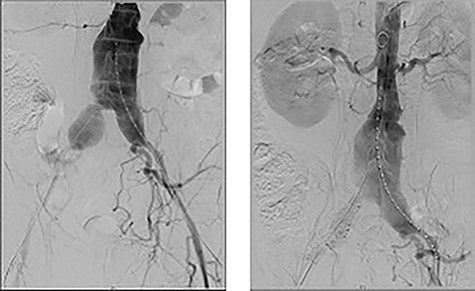

Extensive workup for infective and autoimmune aetiologies such as tuberculosis, syphilis, Q-fever and human immunodeficiency virus (HIV) were negative and serum IgG-4 levels normal (Table 2). He underwent an endovascular aortic aneurysm repair (EVAR) with bilateral iliac branched devices (IBD) during his initial presentation, and his on-table completion angiogram demonstrated good flow through the grafts with no endoleak (Fig. 4).

On table completion angiogram demonstrating good flow through the stent graft and satisfactory flow through renal arteries and iliac branching device with no endoleak.